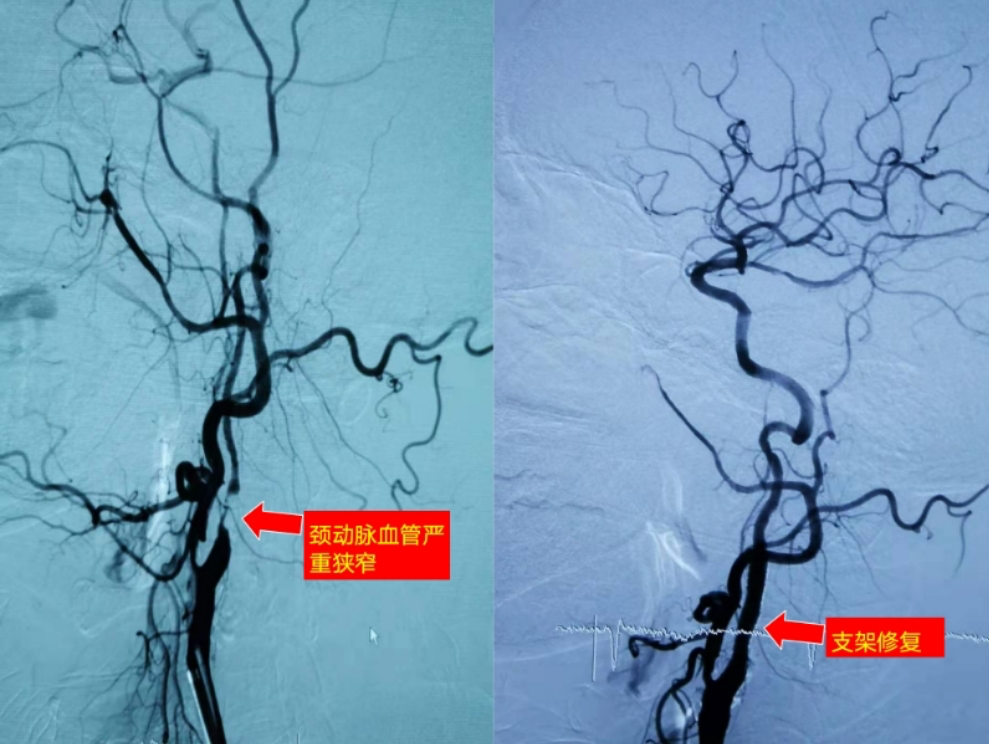

頸動(dòng)脈支架成形術(shù)(carotid artery st enting , CAS)

腦血管病是我國(guó)致死致殘率最高的疾病,其中頸動(dòng)脈狹窄是缺血性腦卒中的常見發(fā)病原因。近年來,隨著介入治療器械和技術(shù)的進(jìn)步,頸動(dòng)脈支架成形術(shù)(carotid artery st enting , CAS)正在成為可能替代頸動(dòng)脈內(nèi)膜剝脫術(shù)(carotid endarterectomy , CEA)的一種微創(chuàng)、安全和有效的頸動(dòng)脈狹窄血流重建手段。

手術(shù)方法:全身肝素化后引入8F指引導(dǎo)管,在路途導(dǎo)引下超選患側(cè)頸總動(dòng)脈,導(dǎo)管停留在血管相對(duì)平直、光滑的部位,距離病變下緣2-3cm,將保護(hù)裝置導(dǎo)引頭根據(jù)病變情況預(yù)塑型,在預(yù)先確定的病變最佳投照角度留取路徑圖,輕柔的通過病變局部送抵巖骨下段后釋放,透視確認(rèn)保護(hù)傘張開良好,引入預(yù)先選擇的球囊送抵病變下方,觀測(cè)患者血壓和心率并囑護(hù)士準(zhǔn)備靜脈推注阿托品,輕柔推送球囊覆蓋病變?nèi)毯蠹訅褐痢皹?biāo)準(zhǔn)壓”,完全膨脹后釋放壓力,后撒球囊并造影確認(rèn)擴(kuò)張效果,引人支架并緩慢推送到位,支架一定要覆蓋病變?nèi)?,撤出支架輸送器后造影觀測(cè)殘余狹窄、支架位置、保護(hù)傘血流通暢情況,如確認(rèn)無異常即可引入保護(hù)傘回收鞘管輕柔通過支架后回收保護(hù)傘。